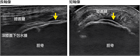

1. 初期病変の描出には超音波が優れ、病期が進行すると単純エックス線でも描出可能となる。